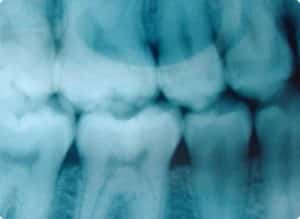

Wenn die Erkrankung der Zähne nicht durch Zufall im Rahmen einer Röntgenuntersuchung des Kieferraumes entdeckt wird, bleibt sie lange verborgen. Das ist das Tückische an dieser Erkrankung. Weil klare Vorzeichen fehlen, wird sie oft erst dann wahrgenommen, wenn einzelne Zähne nicht mehr zu retten sind.

Bei der Parodontose baut sich der Knochen, in dem die Zähne verwurzelt sind, systematisch und im gesamten Kieferbereich immer weiter ab und dadurch verliert der Knochen seine Haltefähigkeit. Das Zahnfleisch zieht sich, ähnlich wie bei der Parodont“itis“, immer weiter zurück.

So werden die Zahnhälse freigelegt und der Zahn erscheint optisch länger. Da der gesamte Vorgang völlig ohne Bakterien abläuft, bemerken die Patienten die Erkrankung auch erst in diesem Stadium, weil einerseits die empfindlichen, freigelegten Zahnhälse immer wieder Schmerzen verursachen, andererseits die Zähne locker werden.